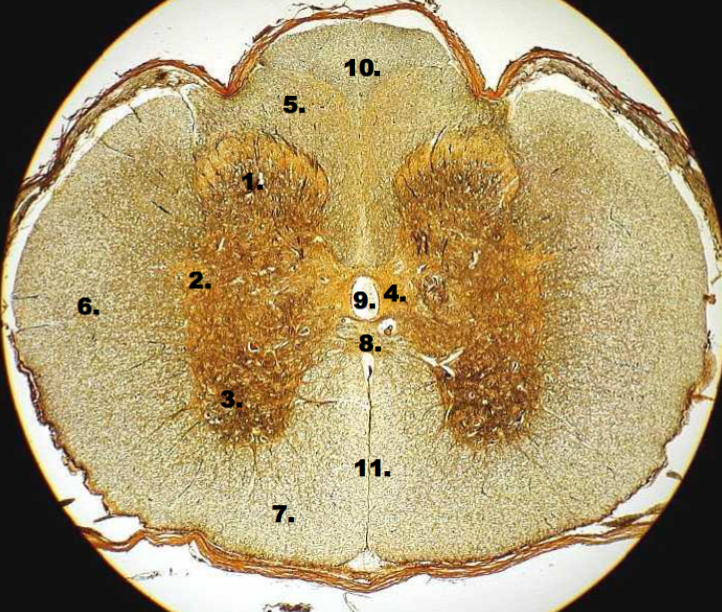

1

posterior horn

2

lateral horn

3

anterior horn

4

gray commissure

5

posterior funiculus

6

lateral funiculus

7

anterior funiculus

8

white commissure

9

central canal

10

posterior median sulcus

11

anterior median fissure